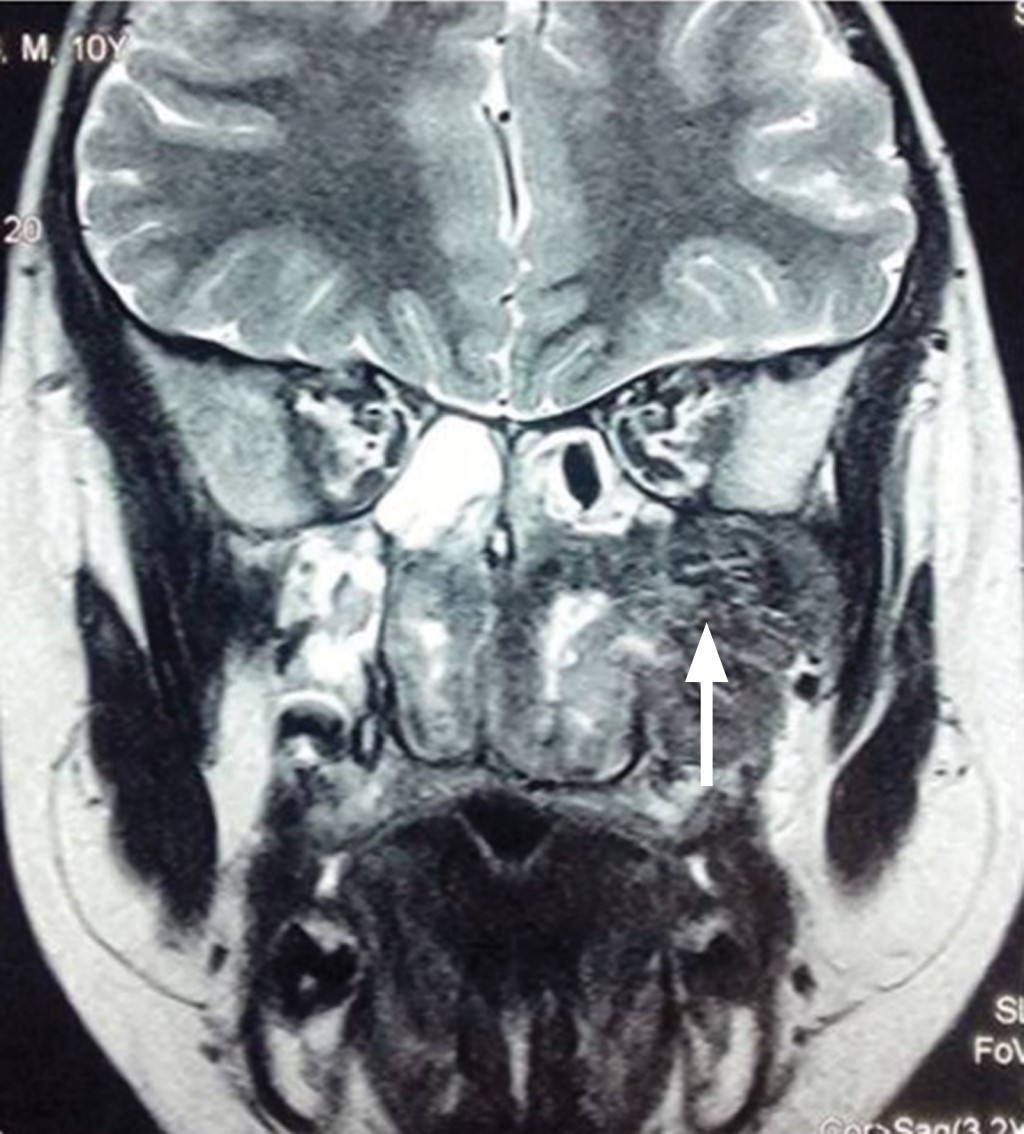

Introduction: juvenile nasopharyngeal angiofibroma is a benign tumor but can cause morbidity and mortality. We present a pediatric patient who had a successful resolution by surgical resection. Clinical case: ten-year-old male, with a history of nine months of unilateral nasal obstruction of approximately, associated with episodes of rhinorrhea, nocturnal hoarseness, mouth breathing, hyposmia and recurrent epistaxis. Imaging studies identified a tumor with irregular borders at the paranasal sinuses, concluding that it was a nasopharyngeal angiofibroma in stage IIb of the Radkowski classification. Tumor embolization is performed, and after 24 hours the tumor is removed by nasal endoscopic surgery. One year after resection, no tumor recurrence was documented. Conclusion: patients with juvenile nasopharyngeal angiofibroma are usually male, in the second decade of life, and with epistaxis as the main manifestation. Its treatment is surgical, with infrequent recurrences.

Figure 2